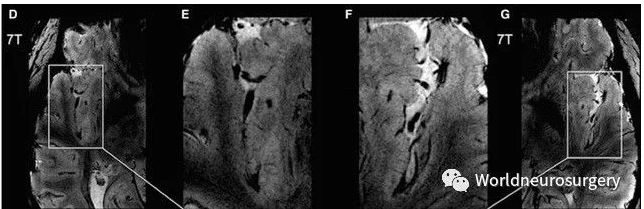

7T图像与活体组织标本对比

局灶性难治性癫痫患者在常规场强MR下未见明显异常,对其行7T磁共振扫描,上图为GRE图像。